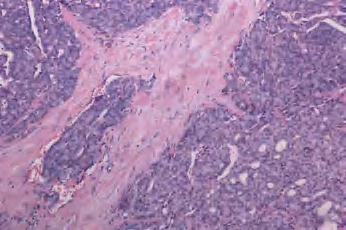

2.镜下 由滤泡细胞组成伴明显的纤维性包膜,缺乏乳头状癌典型的核特征。癌细胞显示不同的形态学变化,可排列成滤泡、实性巢索或小梁。然而,结构上和细胞的非典型特征都不能作为诊断恶性的可靠指证,必须见到肿瘤穿透包膜或(和)血管侵犯。根据侵袭程度分为:微小侵袭性滤泡癌[具有有限的包膜和(或)血管侵犯]和广泛侵袭性滤泡癌[广泛侵犯临近甲状腺组织和(或)血管](图3-54至图3-56)。

图3-54 甲状腺滤泡状腺癌

图3-56 甲状腺滤泡状腺癌